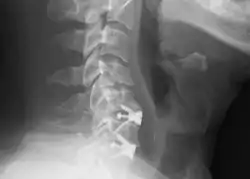

Radiografía cervical lateral que muestra las fijaciones de C5C6 y C6C7, después de una discectomía y fusión cervical anterior.